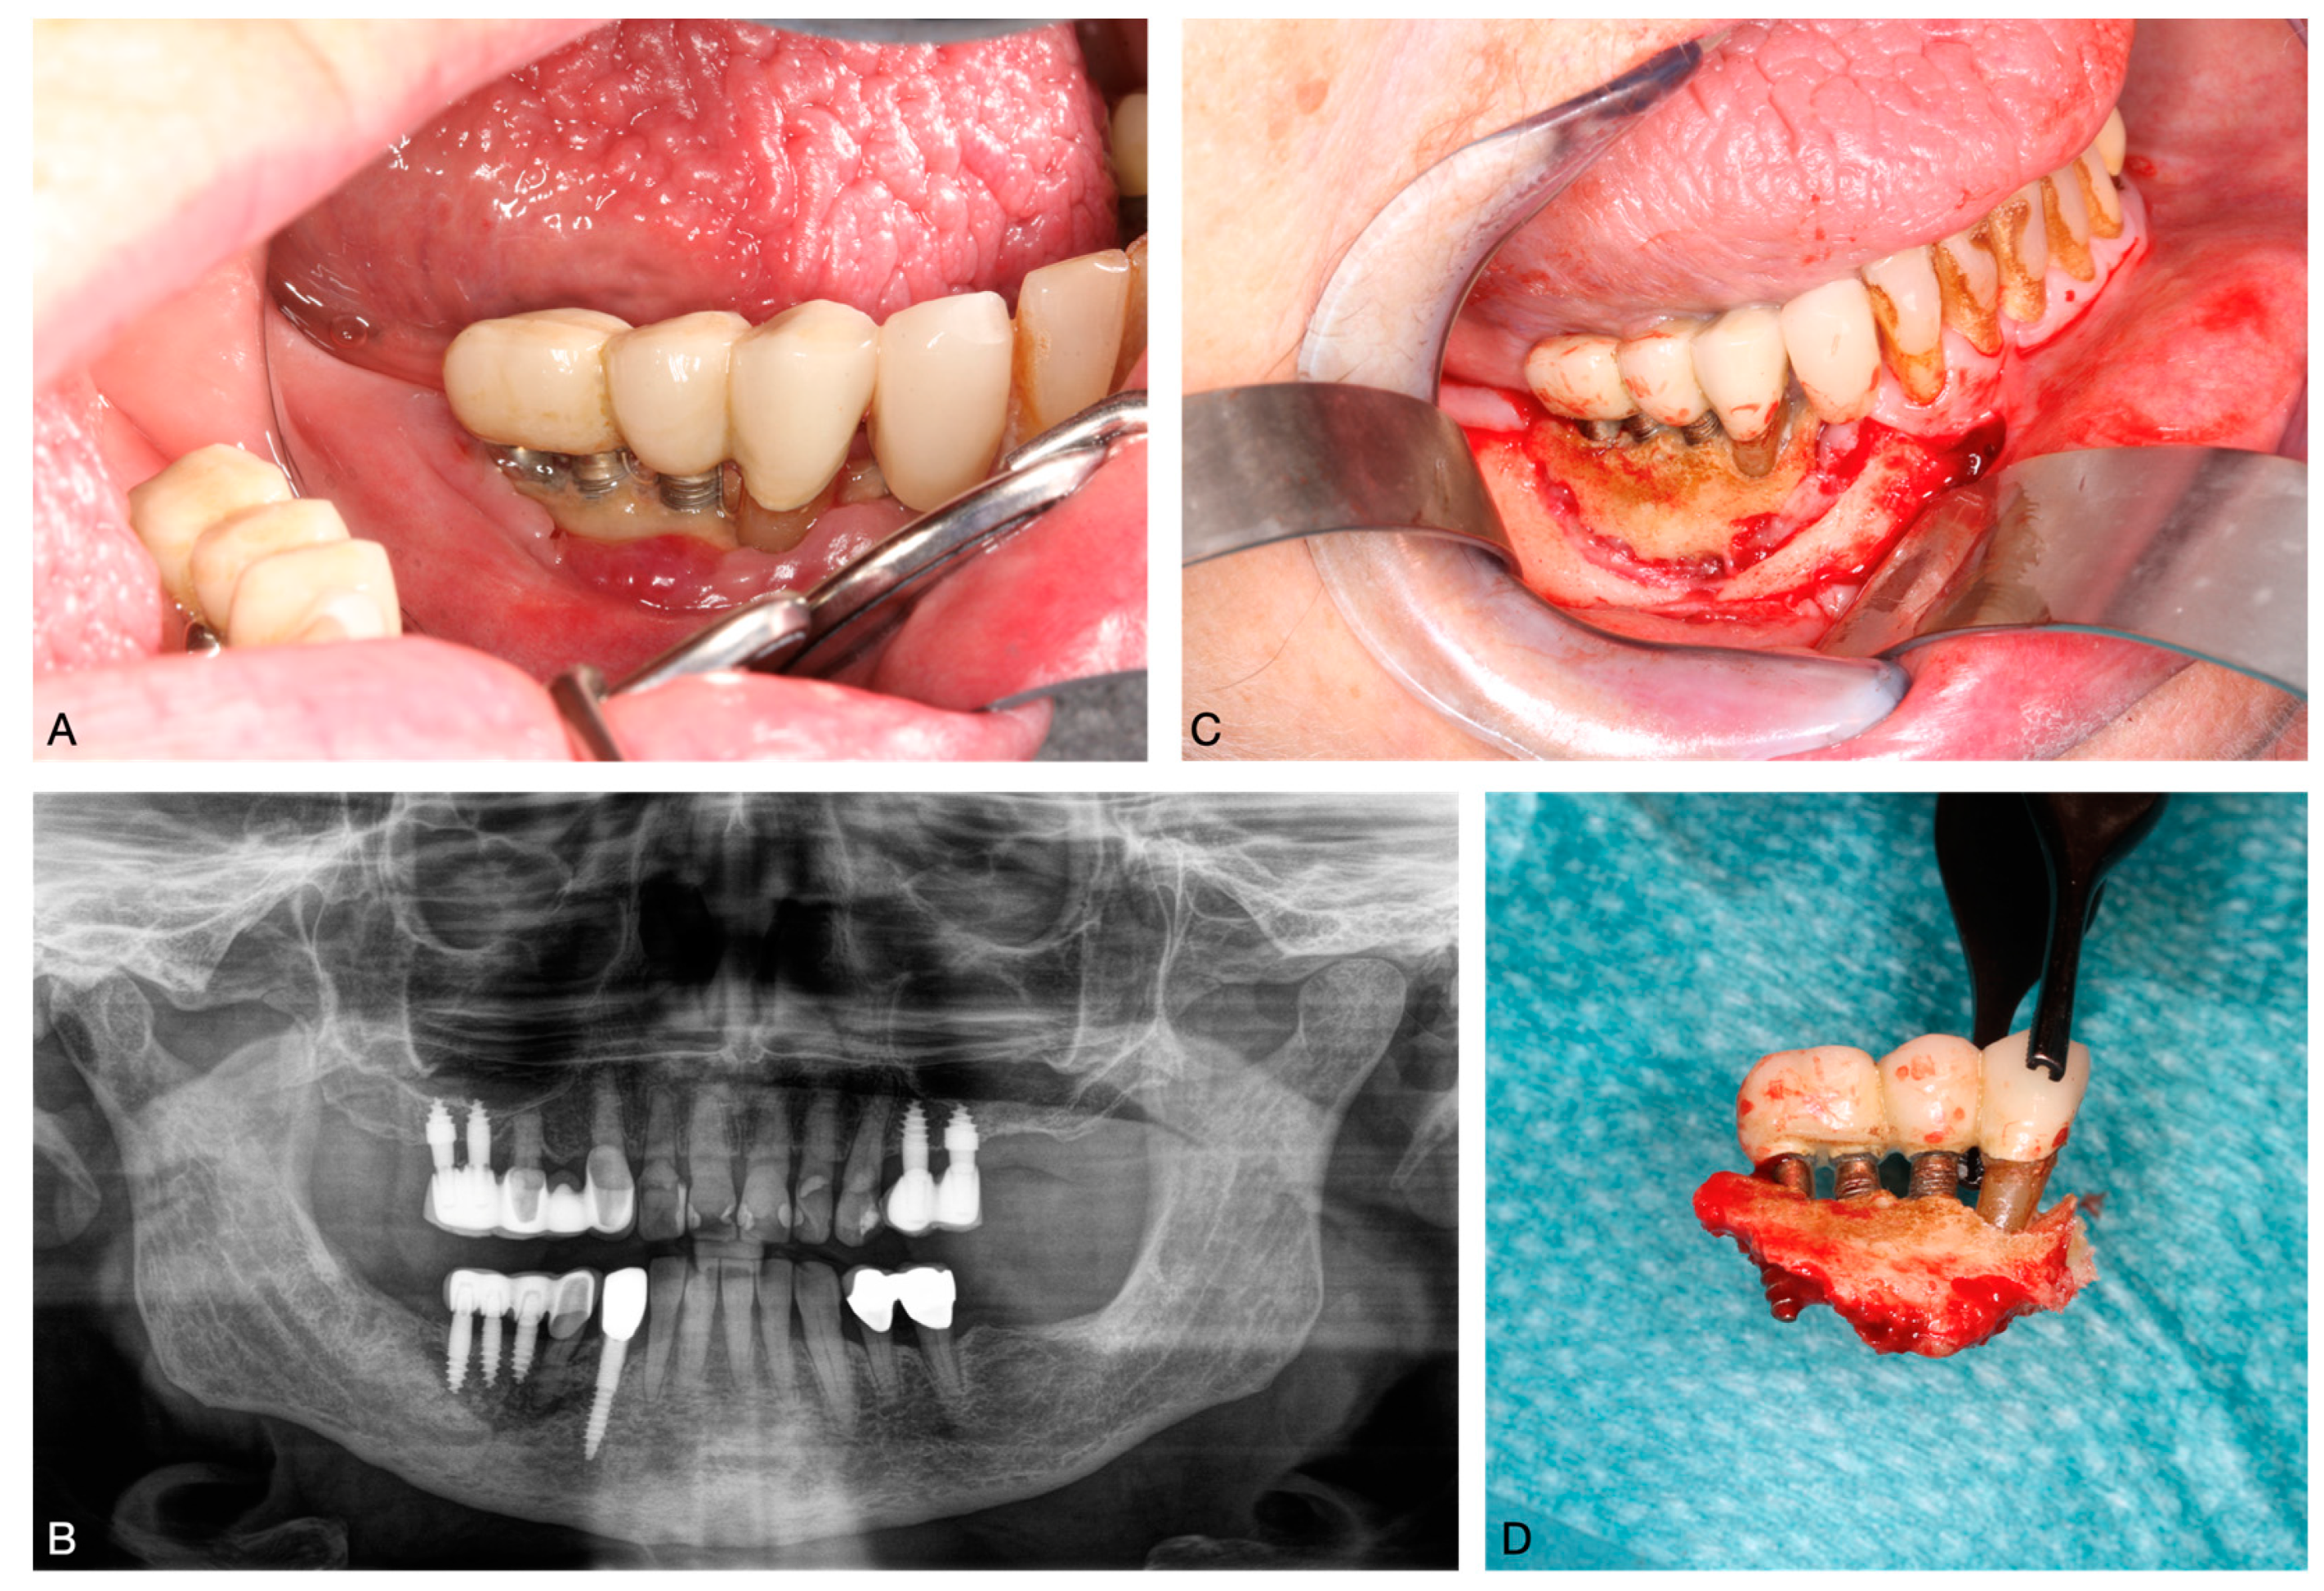

Bisphosphonate-Related Osteonecrosis of the Jaw and Oral Microbiome: Clinical Risk Factors, Pathophysiology and Treatment Options

3. Clinical Risk Factors of BRONJ

5. Treatment Options